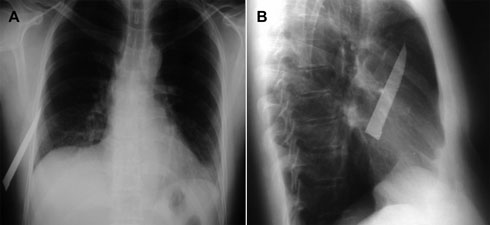

A 55-year-old man suffered a thoracic knife wound during an assault. The wound was sutured by a general practitioner. Five days later, the patient re-presented to another medical centre with chest pains after travelling on two Australian domestic flights, including one for which airport security required him to undergo screening with a metal detector.